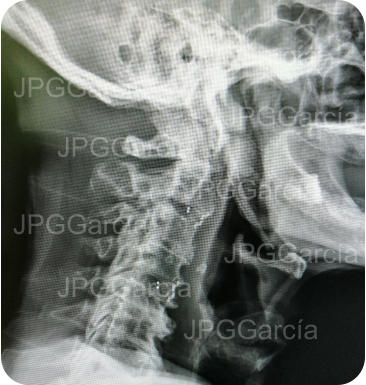

Tratamiento de hernia de disco cervical alta con compromiso medular